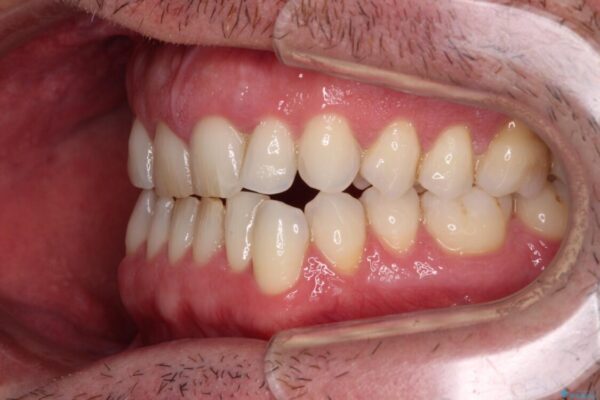

治療前

• 前歯でものを噛みきりたい 目立たない装置でのワイヤー矯正 治療前画像

以前矯正治療を経験されたそうですが、舌の突出癖により上下前歯に隙間ができている様子でした。